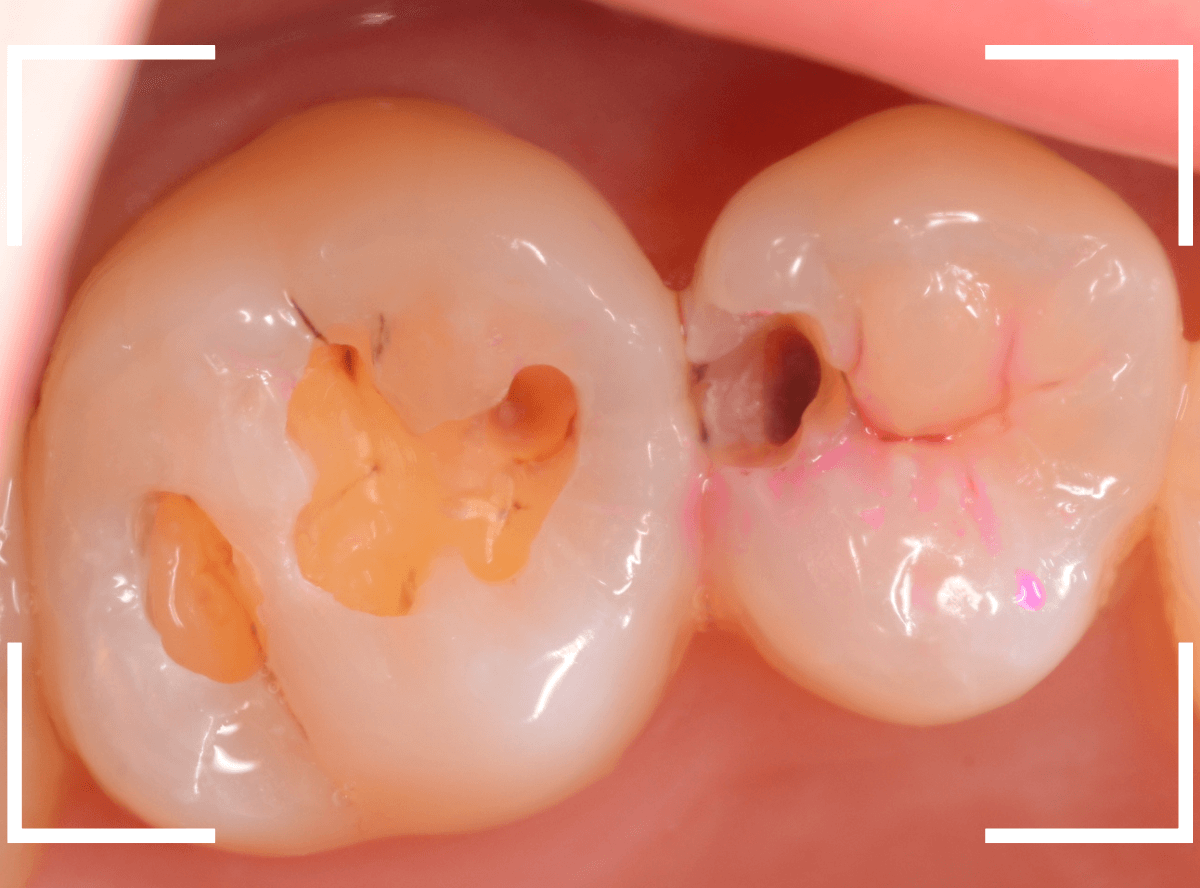

Case.8 大きな虫歯なのに、レントゲンではっきり写らない

こちらも定期検診希望で来院された患者さんです。

お口の中を拝見すると、明らかに虫歯がありました。

3本虫歯になっており、特に中央の小臼歯はかなり大きな虫歯になっているのが予想されます。

治療前にレントゲン写真で虫歯の大きさを確認するつもりが・・・あまりはっきり写ってきません。

患者さんに状況を説明して、歯を少しずつ削りながら虫歯を確認する事になりました。

まず、一番大きな虫歯と思われる部分を小さく削って確認します。

予想通り、虫歯が見えてきました。

隣りの奥歯と一緒に虫歯の治療を進めます。

色が染まっているところがまだ虫歯が残っている部分です。

2本とも、虫歯を全て取り切りました。

特に手前の歯はかなり広めの虫歯になっていました。

最終的に、手前の虫歯の除去も終わったところです。

手前の歯の虫歯は中央の歯まで達していました。

このように明らかに大きな虫歯があると診断されるような状況でも、レントゲン写真でうまく診断できない場合もあります。